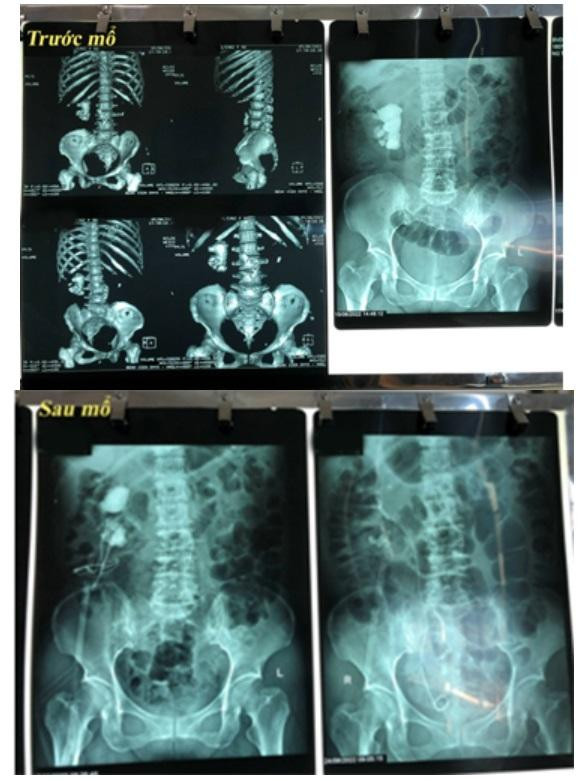

| Hình ảnh chụp X-quang trước và sau phẫu thuật sỏi san hô phức tạp. Ảnh: BV. |

Sau khi được BSCKI. Nguyễn Đức Hùng, Phòng khám Thận niệu - Nam khoa kiểm tra và tư vấn thực hiện các xét nghiệm cận lâm sàng, kết quả cho thấy bệnh nhân có sỏi san hô phức tạp, lấp đầy các xoang thận với kích thước 6 - 7cm.

Kết thúc ca mổ, sỏi được lấy khỏi các vị trí phức tạp trong đài thận. Sau phẫu thuật 4 tiếng, sức khỏe bệnh nhân ổn định.

Ngày thứ 2 sau mổ, bệnh nhân được rút ống thông tiểu, đau ít và có thể vận động nhẹ. Sau 1 tuần, các bác sĩ tiến hành tán sỏi lần hai qua đường hầm và đạt kết quả tốt.